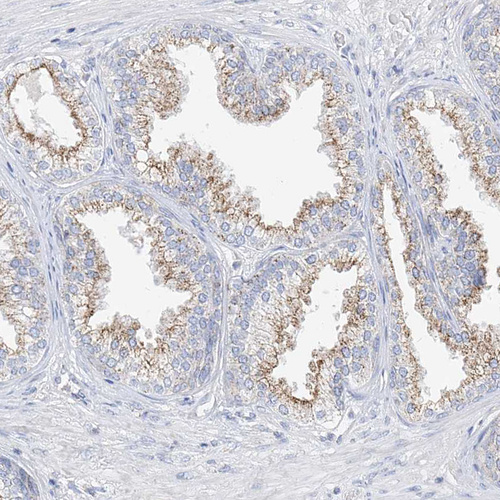

Immunohistochemical staining of human small intestine shows moderate cytoplasmic positivity in glandular cells.